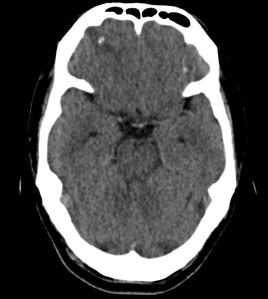

A young Indian national presented with his first ever episode of generalized tonic-clonic seizures and was hospitalized. He was previously healthy, vegetarian, and had been based in Singapore for the past 3 years, working in the construction industry. A plain CT head performed at the emergency department showed a spot of calcification at the right frontal lobe with surrounding oedema.

Subsequently, an MRI brain was performed.